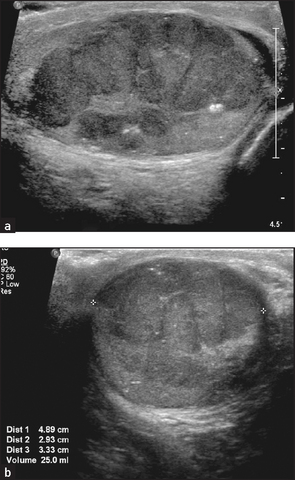

5. Ultrasound to look at renal size and for any renal mass or urinary obstruction (ureters and bladder); and by arterial Doppler to measure renal blood supply. Ultrasound of the scrotum is used to identify scrotal masses. Note the kidneys are usually both small on ultrasound in chronic kidney disease, but the exceptions include diabetes mellitus and amyloid or polycystic kidneys.

Figure 19.5 Ultrasound of polycystic kidneys. There are multiple discrete cysts, the largest 1.2 × 1.2 centimetres. (From Kaplan BS, Meyers K. Paediatric nephrology and urology: requisites, 1st edn. Mosby, 2004.)